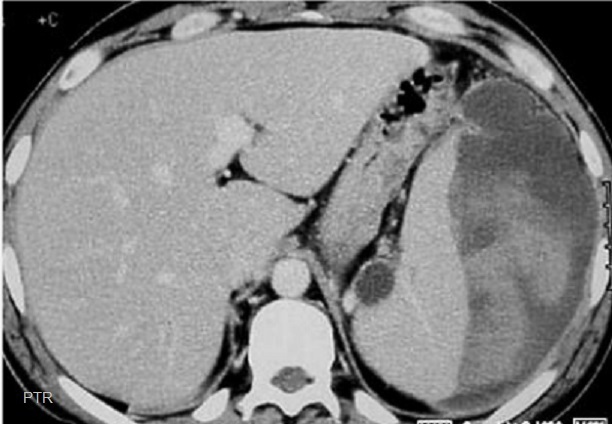

Aspect

radiologique une rate sur numeraire a inferieure de

la la rate principale ( fleche rouge ) .Ce coupe

frontale ( coronal) se prise au temps de precoce

apres injection de contrast intra veineuse . Sa

parenchyme est rehaussement hyperdensité heterogène

au temps de precoce . Image radiologique TDM plus C+

coupe coronal . |